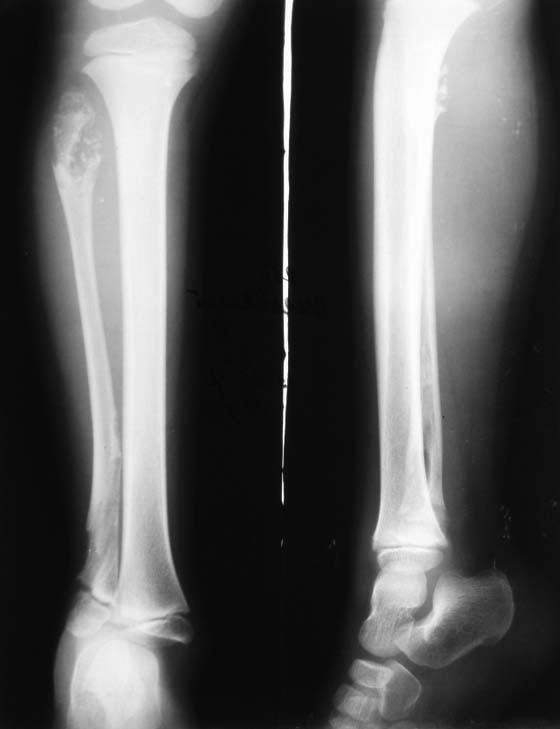

Подскажите, пожалуйста, тактику лечения этому ребенку при болезни Олье...

... с поражением малоберцовой кости и подвывихом стопы

Мне кажется, что здесь необходимо стабилизировать вилку голеностопного сустава низведением наружной лодыжки. Желательно панорамный снимок нижних конечностей сделать и выяснить если еще очаги дисхондроплазии.